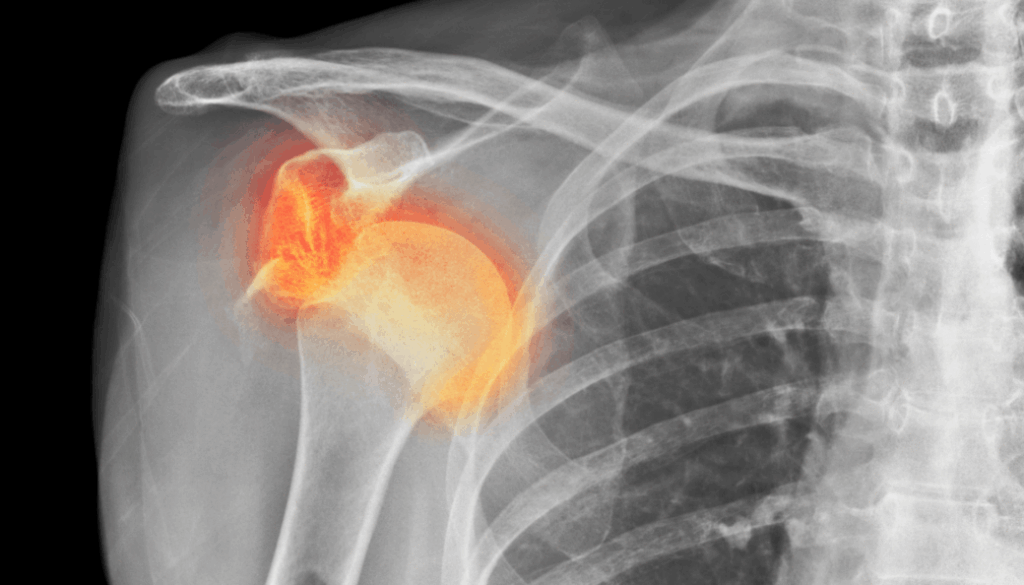

Von allen Gelenken im menschlichen Körper, die auskugeln, ist die Schulter bei weitem das häufigste. 1 In 50% aller Gelenke, die auskugeln, ist es die Schulter. Das ist aber nicht verwunderlich, wenn man bedenkt, dass die Schulterpfanne eigentlich gar nicht so groß ist. Eine Schulterauskuglung wird in der Regel durch eine von drei Ursachen ausgelöst:

Verglichen mit der tiefen knöchernen Hüftpfanne ist die Schulterpfanne eher als kleine Schale zu bezeichnen. Diese Schale wird durch das Labrum noch verstärkt. Das Labrum ist einen Knorpelring, der direkt an der Gelenkpfanne der Schulter ansetzt. Das Labrum ist wiederum mit den Muskeln der Rotatorenmanschette verbunden, die zusammen die Schulterkapsel bilden. Sie sollten diese Muskeln als eine dynamische Gelenkpfanne betrachten, die zur Stabilisierung des Schulterkopfes beiträgt, indem sie genau im richtigen Moment angespannt wird, wenn sie ihre Bewegungen ausführen.

Für die Anforderungen, die wir an die Schulter stellen, ist ihre Anatomie sehr sinnvoll. Die minimale Gelenkpfanne ermöglicht es uns, den Arm frei in allen Richtungen zu bewegen. Durch diese Bewegungsfreiheit wird die Stabilisierung der Schulter für den Körper jedoch schwieriger.

In ungefähr 75% der Fälle findet die Auskuglung nach vorne statt. Dies sehen wir am meisten, wenn die Auskuglung beim Sport oder bei einem Sturz entsteht. In 20% der Fälle findet die Auskuglung nach hinten statt, zum Beispiel beim Verkehrsunfall. Diese Diagnose wird häufig übersehen, da sie bei der körperlichen Untersuchung oft weniger auffällig ist als eine Auskuglung nach vorne. 3 In 5% der Fälle findet die Auskuglung in verschiedenen Richtungen statt (typischerweise bei einer Hypermobilität). 4

In einigen Fällen können bei einer traumatischen Schulterluxation mehrere Strukturen beschädigt werden. Zunächst kann einmal das Bindegewebe der Kapsel und/oder des Labrums gedehnt werden oder reißen. Zum anderen kann sich eine knöcherne „Bankart-Läsion“ entwickeln, bei der es durch den Aufprall zu einer Fraktur am unteren Ende der Schulterpfanne kommt. Dies geht häufig mit einer „Hill-Sachs-Läsion“ einher, einer Delle in der Schulterkopf selbst. Eine Röntgenaufnahme der Schulter kann dies entweder zeigen oder ausschließen.